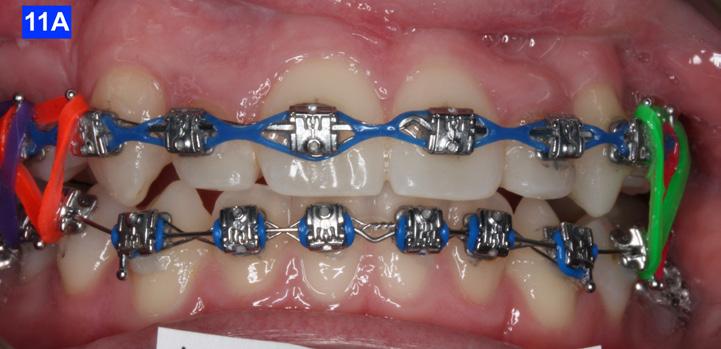

Count down on retention

After 42 months of treatment, Goodman Torquing springs (Ortho Arch) were crimped on the final arch wire (a. 019 x 025 SS) to create a lingual crown moment (lingual torque) and buccal root moment to upright the displaced maxillary lateral incisors.9 Goodman Torquing springs were left in until the end of the treatment (Figure 11 – B, C).

Three months before de-bracketing, while the patient had a .019 x .025 SS arch wire in the maxilla and the mandible, we appointed her for “Count down on retention.” The full arch wire was left in the maxilla, however, in the mandible, it was cut and bent-in, just distally to cuspids. Two triangular elastics were placed per sextant (1/4”– 4.5 oz.) for refinement of the tooth-to-tooth inter-digitation (Figure 13 - A, B, C).8

Figure 10E: Maxilla, occlusal view Figure 10F: Mandible, occlusal view Figure 11A: Frontal view Figure 12A: Class III elastic, right lateral view Figure 12B: Class III elastic, left lateral view Figure 11B: Goodman torquing spring Figure 11C: Goodman torquing spring in situ